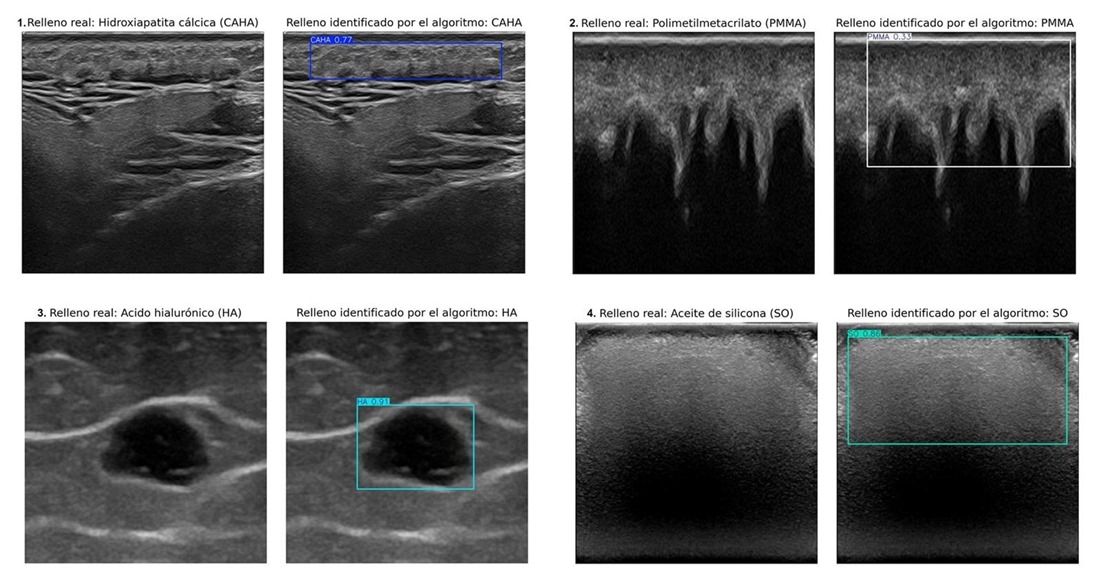

La ecografía, aunque es el método más eficaz para detectar estos rellenos, requiere una amplia experiencia clínica para interpretar las imágenes. La IA desarrollada por la doctora Ximena Worstman de la Universidad de Chile y los profesores Manuel Lozano y Francisco J. Rodríguez de la Universidad de Granada integra aprendizaje profundo para identificar rellenos de hidroxiapatita cálcica, ácido hialurónico, polimetilmetacrilato y aceite de silicona.

El sistema se ha entrenado con equipos ecográficos de diversa complejidad, desde portátiles hasta dispositivos de alta gama, para garantizar su adaptabilidad en distintos entornos clínicos. Este desarrollo representa un paso importante hacia una medicina estética más precisa, accesible e innovadora, atendiendo un problema clínico creciente en la era de la belleza inyectable.